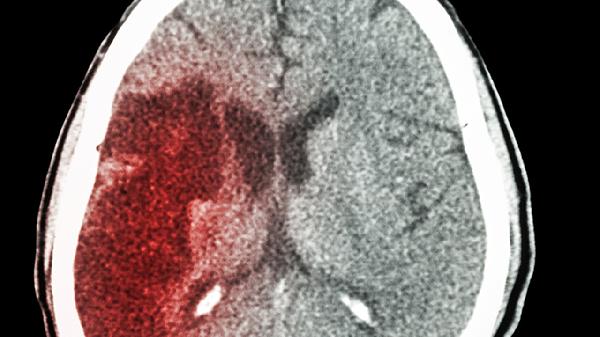

2、颅内压增高

术后血肿复发或脑水肿可能导致颅内压升高,刺激脑干网状结构引发躁动。患者常伴有剧烈头痛、喷射性呕吐等症状。需紧急复查头颅CT,使用甘露醇注射液降低颅压,严重时需行去骨瓣减压术。监测瞳孔变化和意识状态是关键。